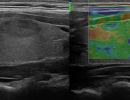

Με την τριπλή μελέτη του Θυρεοειδούς Αδένα, που περιλαμβάνει το B-Μode, το Έγχρωμο Υπερηχογράφημα και την Ελαστογραφία, γίνεται μια ολοκληρωμένη χαρτογράφηση του θυρεοειδούς αδένα. Το περίγραμμα, η αγγείωση και η ελαστικότητα του αδένα, καθώς και η υφή μίας πιθανής βλάβης αξιολογούνται με ακρίβεια και αξιοπιστία.